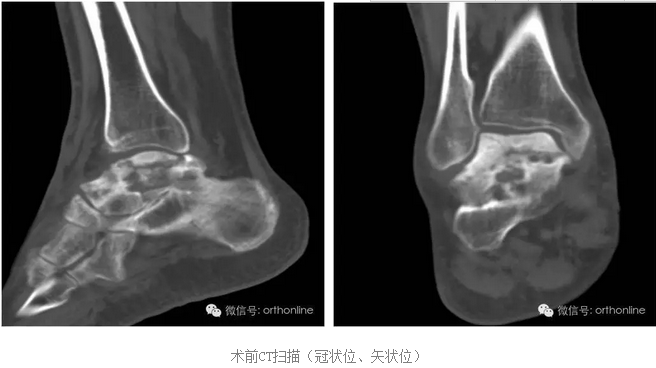

假体制作完全忠实于患者个体的解剖结构,术前将健侧的骨性解剖数据进行镜像处理,获得个性化假体数据源;3D打印完成后再将假体扫描,与数据源进行耦合对照检测;假体植入后扫描患肢,检测与数据源耦合性能;

根据距骨不同部位力学需求,选用力学性能匹配的金属材料和打印方式,完成力学性能的个体化。突破踝关节置换的禁忌: